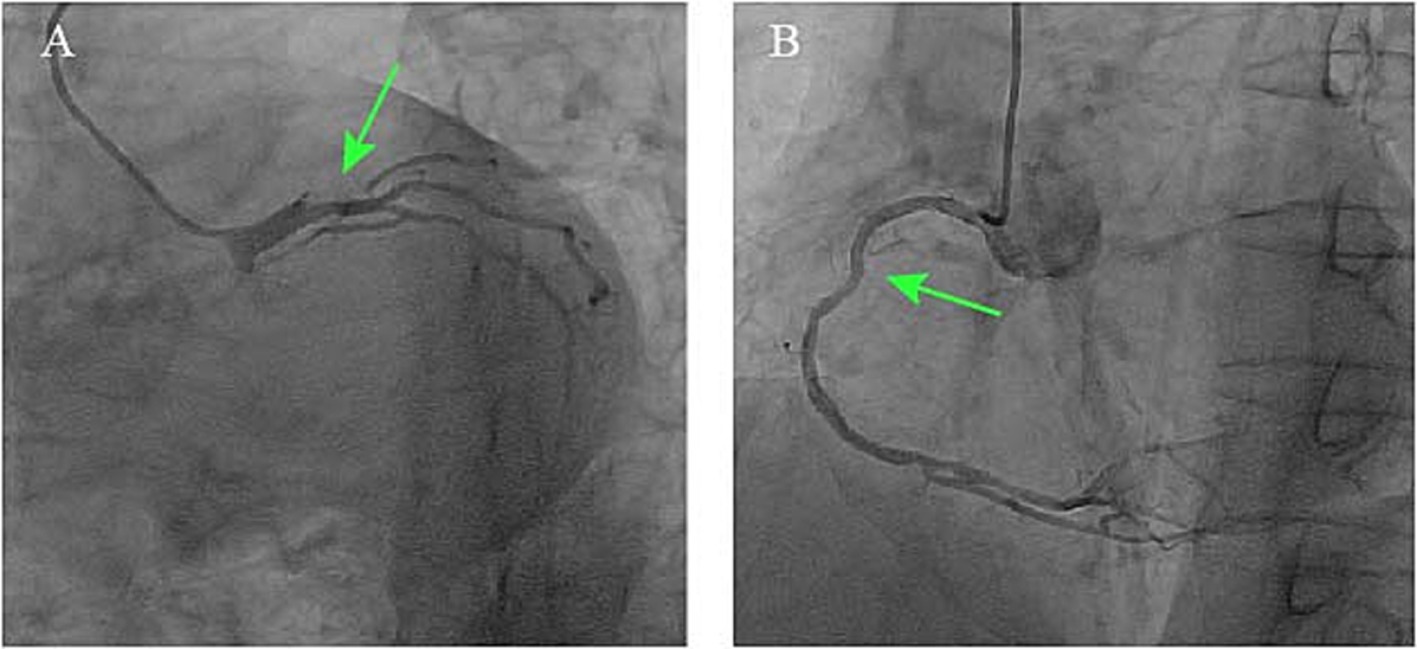

Given the patient’s indeterminate symptom onset timeline, absence of acute anginal symptoms, and hemodynamic stability, guideline-directed medical therapy for heart failure was initiated, comprising antiplatelet therapy, statins, beta-blockers, angiotensin-converting enzyme inhibitors, and mineralocorticoid receptor antagonists. Antibiotic treatment was deferred until completion of the diagnostic workup. After 10 days of medical management, the patient had no significant symptoms of heart failure. A follow-up echocardiogram after 10 days of medical therapy showed persistent severe left ventricular dysfunction (EF 29%) and unchanged valvular abnormalities. Selective coronary angiography demonstrated a critical stenosis at the distal left main coronary artery, specifically involving the ostio-proximal segment of the LAD artery with diffuse disease involving the right coronary artery. Notably, grade 2 intercoronary collateral circulation (Rentrop classification) was observed between the right and left coronary systems (Figure 3). To further evaluate systemic atherosclerotic burden, a carotid artery ultrasound was performed, revealing a normal intima-media thickness (CIMT) of 0.7 mm bilaterally, with no evidence of plaque formation.

Figure 3

Coronary angiograms demonstrating (A) critical stenosis at the distal left main coronary artery involving the LAD ostio-proximal segment (green arrow) and (B) right coronary artery diffuse disease with Rentrop grade 2 collaterals.